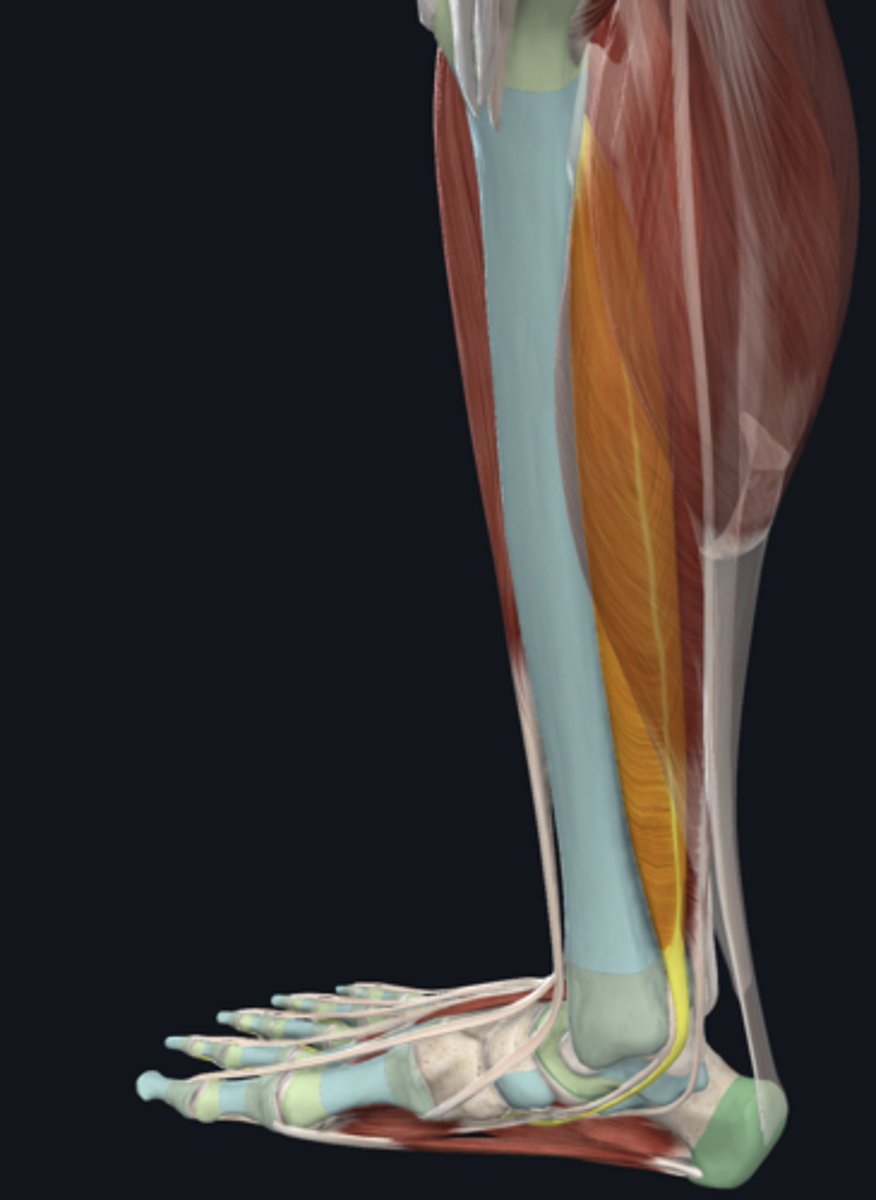

Soleus

Plantaris

Flexor digitorum longus

tendon in tarsal tunnel

Flexor hallucis longus

tendon in tarsal tunnel

Tibialis posterior

tendon in tarsal tunnel